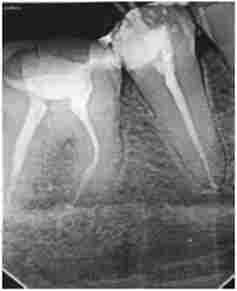

Мал. 10.2. Візіограмма. Пацієнт Н., 27 років. Діагноз: К04.6 «периапикальную абсцес з порожниною 1.1 зуба»:

кореневої канат зуба 1.2 пломбувати до верхівки, пломбувальний матеріал в зубі 1.1 визнавств за верхівку кореня